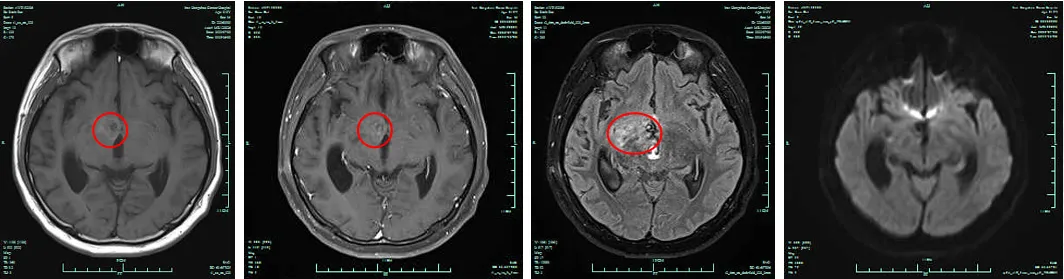

图1. 放疗前头颅MRI检查结果(2022.7.20)

图2.放疗前脊髓MRI检查结果(2022.7.22)